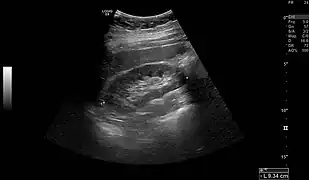

- Normal adult right kidney as seen on abdominal ultrasound with a pole to pole measurement of 9.34 cm